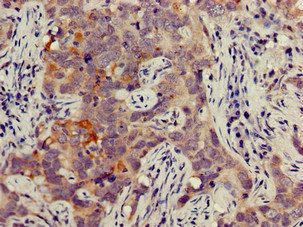

JAG1 Antibody (CSB-PA01949A0Rb)

驗證數(shù)據(jù)

Immunohistochemistry of paraffin-embedded human pancreatic cancer using CSB-PA01949A0Rb at dilution of 1:100